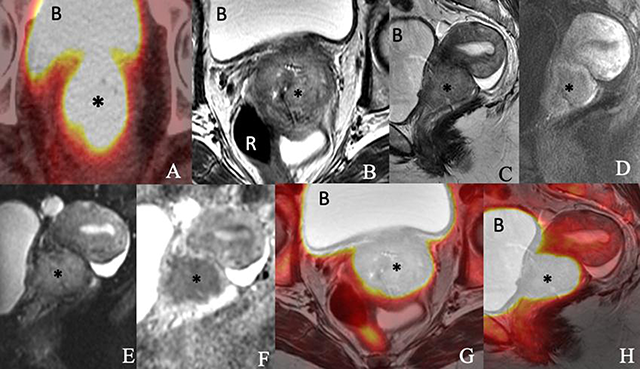

Figure 1

Images of a 76-year-old woman with newly diagnosed squamous cell carcinoma of the cervix consisting of an (A) axial PET/CT, (B) axial T2-weighted, (C) sagittal T2-weighted, (D) sagittal postcontrast T1-weighted, (E) sagittal diffusion-weighted (F) sagittal apparent diffusion coefficient map of MRI, (G) axial T2-weighted PET/MRI and (H) sagittal T2-weighted PET/MRI images show a 5.4 × 4.6 × 4.1-cm enhancing FDG-avid cervical mass (*) invading the parametrium and extending into the vaginal fornices and lower uterine segment. The mass exhibits restricted diffusion. The bladder (B) and rectum (R) appear to be uninvolved.